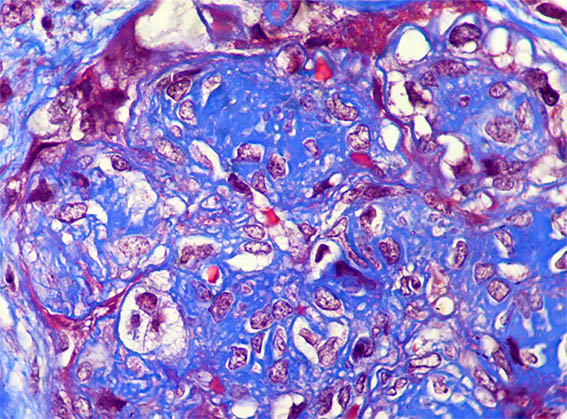

Figura 4. Tricrómico de Masson, X400.

Figura 5. Tricrómico de Masson, X400.

Figura 6. Tricrómico de Masson, X400.